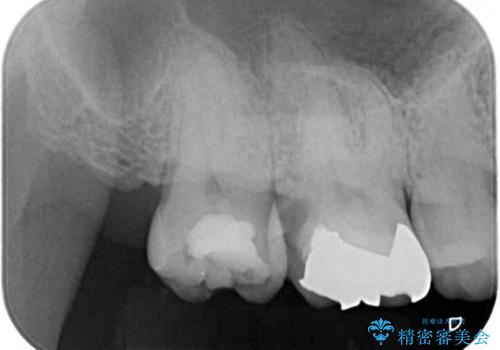

- むし歯治療途中で放置していた奥歯から、歯磨きの度に出血するとのことで来院された患者様です。

隣接する部分の間のむし歯が歯肉の奥深くにまで及んでおり、歯肉が腫れやすい状態となっていたため、歯肉の切除並びに歯槽骨の形態修正を行い、虫歯が歯肉の外に出てくるようにした上で、オールセラミックにて補綴することとしました。